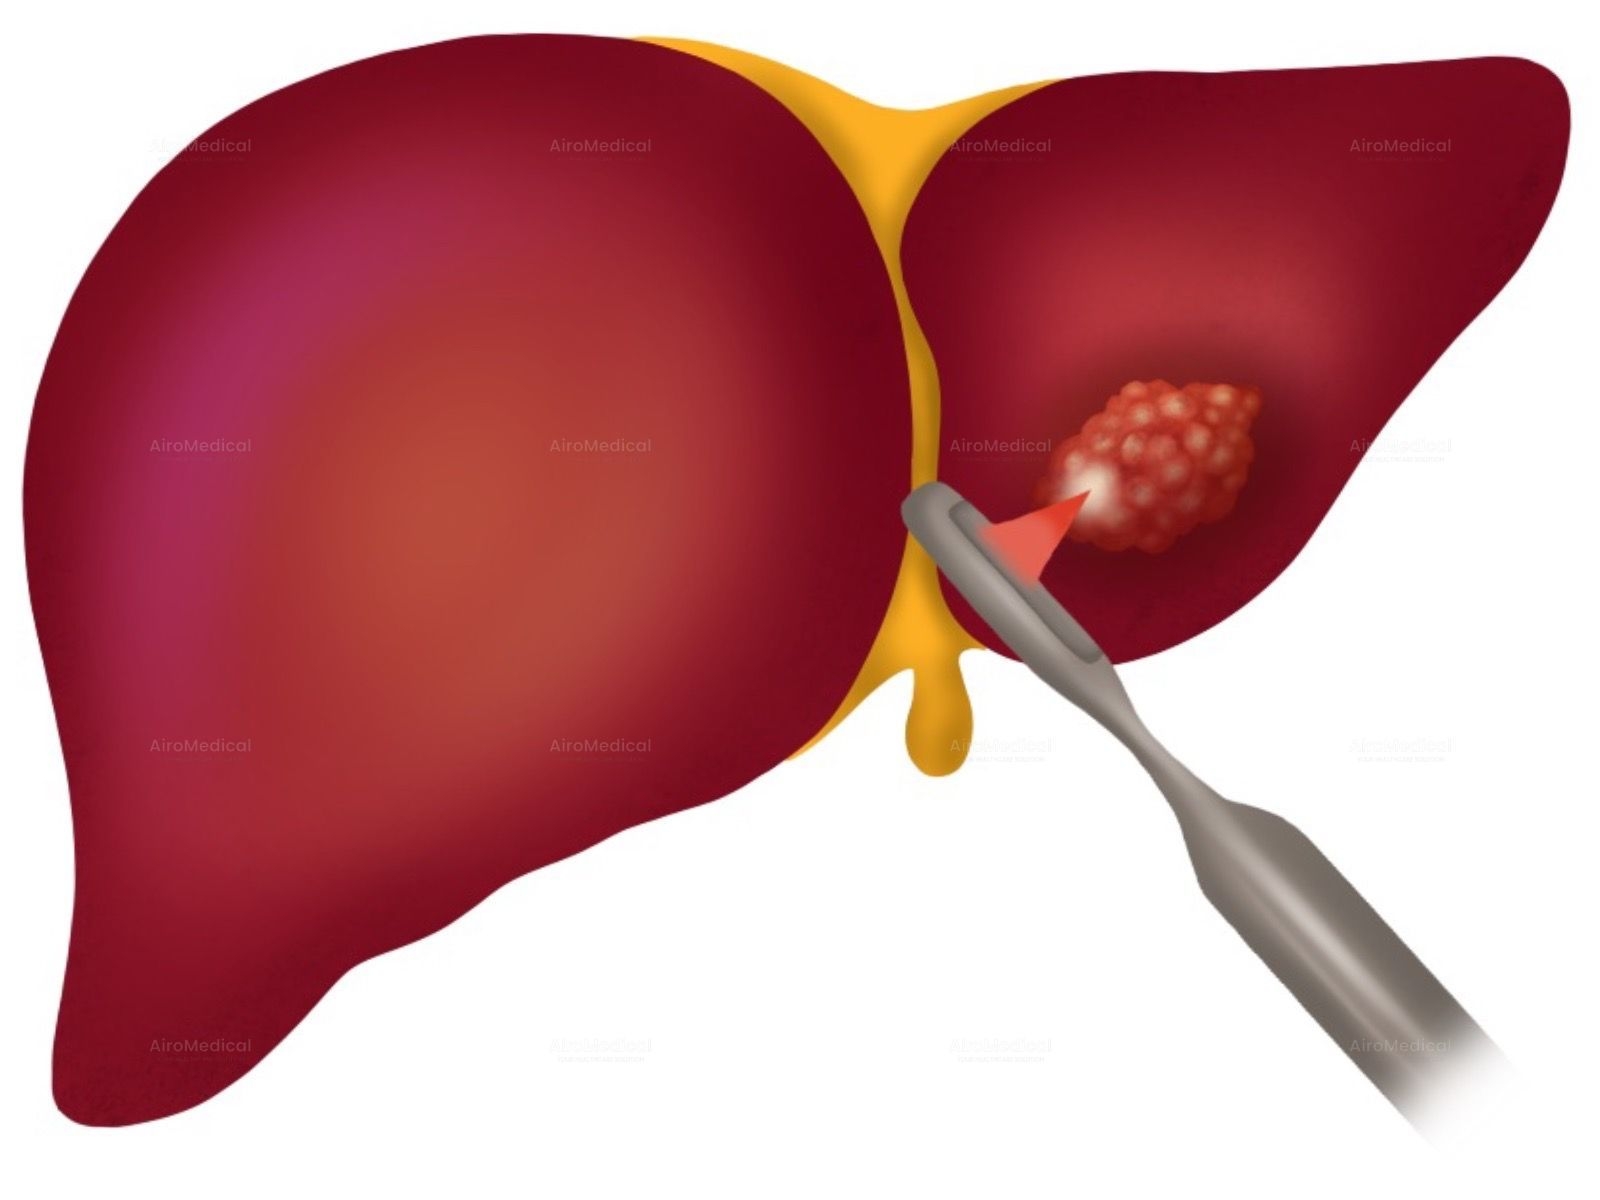

Is University Hospital Frankfurt suitable for patients with cancer?

It is one of the largest institutions dealing with cancer treatment. The oncology unit has a spiral tomograph, a gamma knife, PET, and other latest-generation equipment. Moreover, the team has performed hundreds of successful operations to treat the most complex oncological diseases.